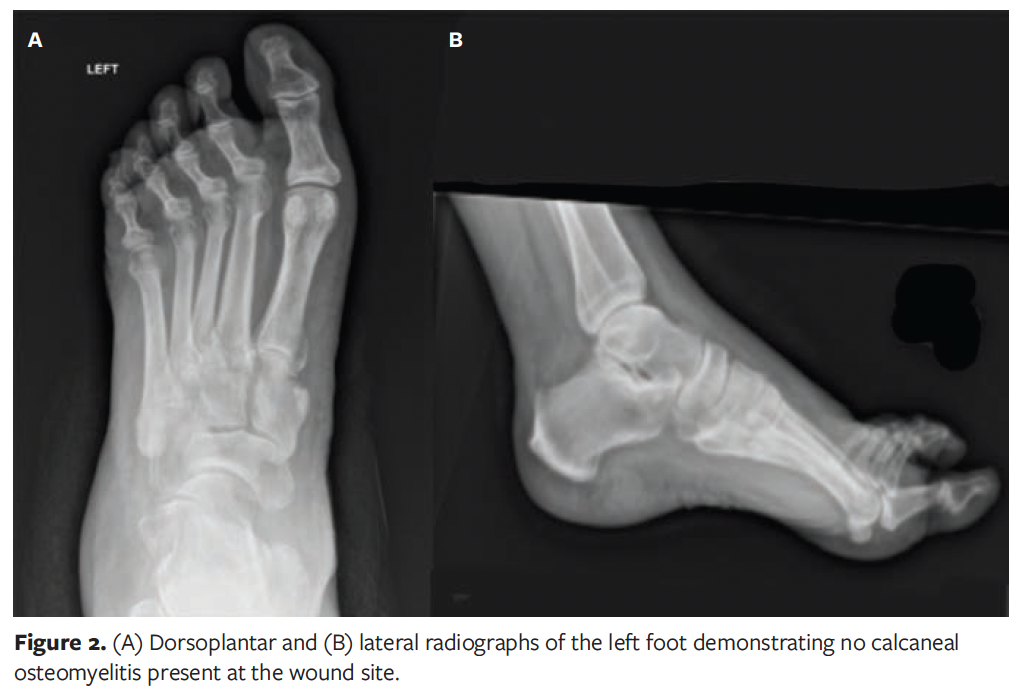

At the time of presentation to the authors of this case report, patient had been presenting on a weekly basis to an outside podiatrist for approximately 8 weeks (Figure 1). In addition to receiving care from the outpatient podiatrist, the patient had been following up intermittently with her vascular surgeon, who believed the patient did not need further surgical intervention and deemed her to have “mild arterial disease” at the time of this wound. The patient’s treatment included routine debridement, application of silver-enhanced alginate (ie, silver alginate), and off-loading with a tall controlled ankle motion boot/removable cast walker. During this time, the patient was monitored for signs of osteomyelitis to the left calcaneus with serial foot radiographs and a magnetic resonance imaging (MRI), which showed no evidence of calcaneal osteomyelitis (Figure 2). The patient was also monitored for signs of worsening arterial status to the lower extremities, with no status change during the progression of this wound. She was deemed medically optimized from a vascular surgery standpoint.